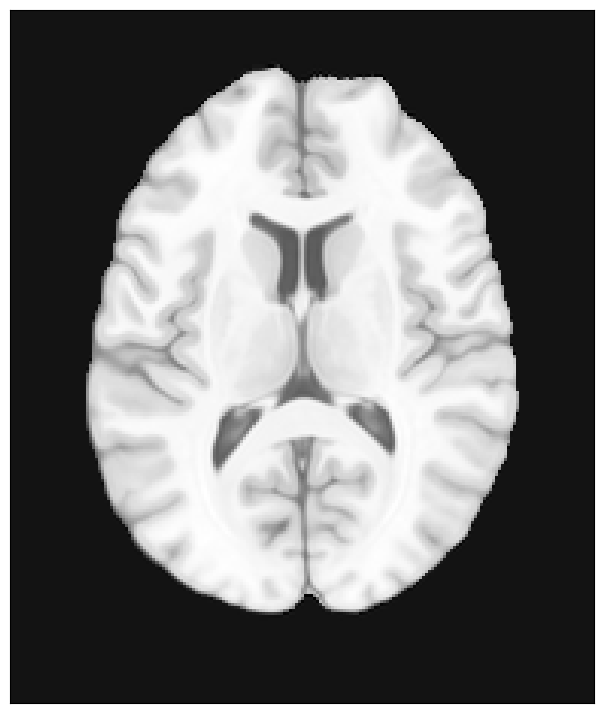

Data: a brain

Let’s start getting some brain image model to work with, select a particular axial slice at the middle of it and visualize it.